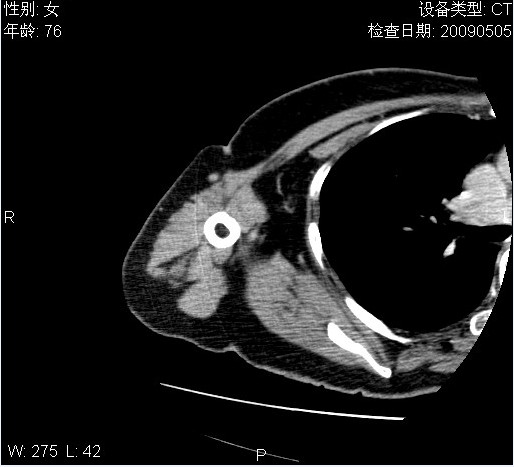

标题: CT19811:女,76岁,右上臂肿物1个月 [打印本页]

标题: CT19811:女,76岁,右上臂肿物1个月

使用了造影剂,可惜效果不太好

右肱骨上段软组织内见梭形低密度影,边界清楚,最长径约54mm.

病理结果:脂肪瘤。术中见肱骨骨膜受侵,有出血,量不详。

当时诊断意见:右肩三角肌内蔓状血管瘤(先天性动静脉瘘)。

本人对病理结果有个疑问:单纯的脂肪瘤内为什么有条状软组织影,那应该脂肪肉瘤才对啊?

该病例增强效果欠佳,由于经验欠缺,我们注射对比剂是由下肢足背静脉给药。注速2.0。虽然如此,但我们可以看到肿块内部条状软组织影是强化的,而且是连续的,并可见供血动脉是由腋动脉的其中一支即肩胛下动脉分出。从这些征象我们可以得出诊断:蔓状务血管瘤。

可病理偏偏为脂肪瘤,我怀疑取材有问题。因为蔓状血管瘤异常扩张的静脉外周是脂肪成分,它可以侵犯肌组织及骨骼。当取材于外周,那当然是脂肪瘤。此时我认为临床的最终诊断不应单从病理出发,应该综合考虑。